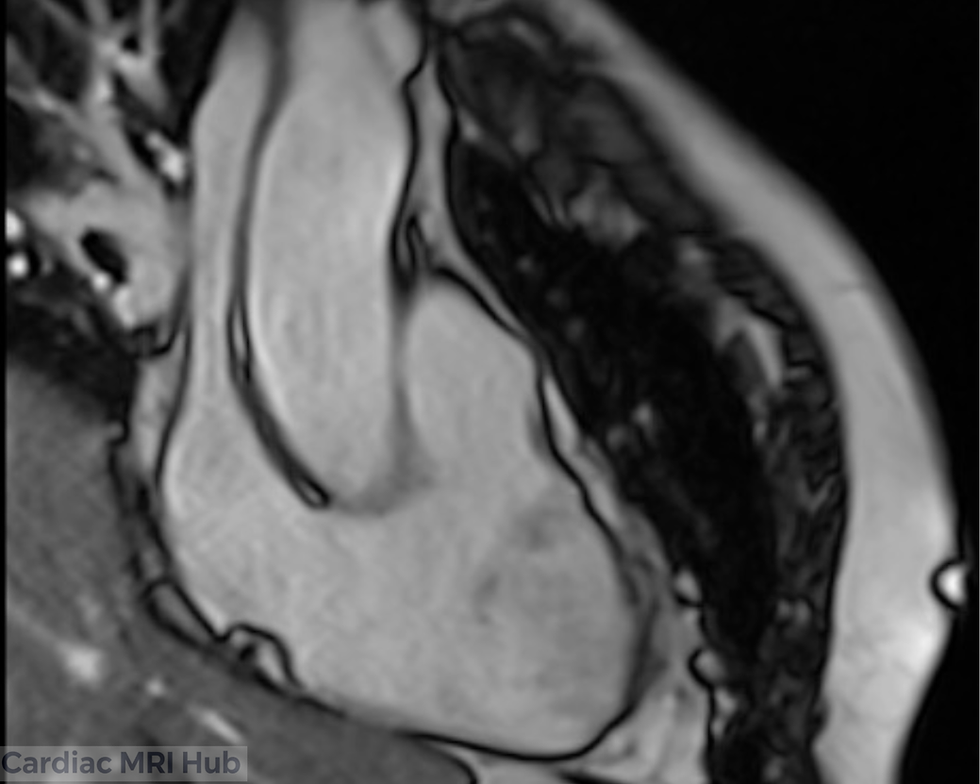

Right Ventricular Outflow Tract View

The right ventricular outflow tract (RVOT) is a critical anatomical region connecting the right ventricle to the pulmonary artery. Accurate visualization of this area is essential for evaluating right ventricular function, detecting outflow tract abnormalities, and assessing the pulmonary vasculature. In cardiac MRI, obtaining optimal sagittal and coronal views requires careful planning and precise positioning. This guide covers key planning techniques for both the sagittal RVOT view and the coronal pulmonary artery view to ensure comprehensive evaluation of right heart structures.

Sagittal Right Ventricular Outflow View Planning

Orientation: The sagittal right ventricular outflow view is typically obtained from a plane that intersects the right ventricle and its outflow tract, ensuring optimal visualization of these areas.

Field of View: The field of view should encompass the entire right ventricle and outflow tract, ensuring that no critical anatomical structures are overlooked.

Right Ventricle: Detailed evaluation of right ventricular size, wall motion, and overall function.

Outflow Tract: Assessment of the right ventricular outflow tract and its relationship with the pulmonary artery.